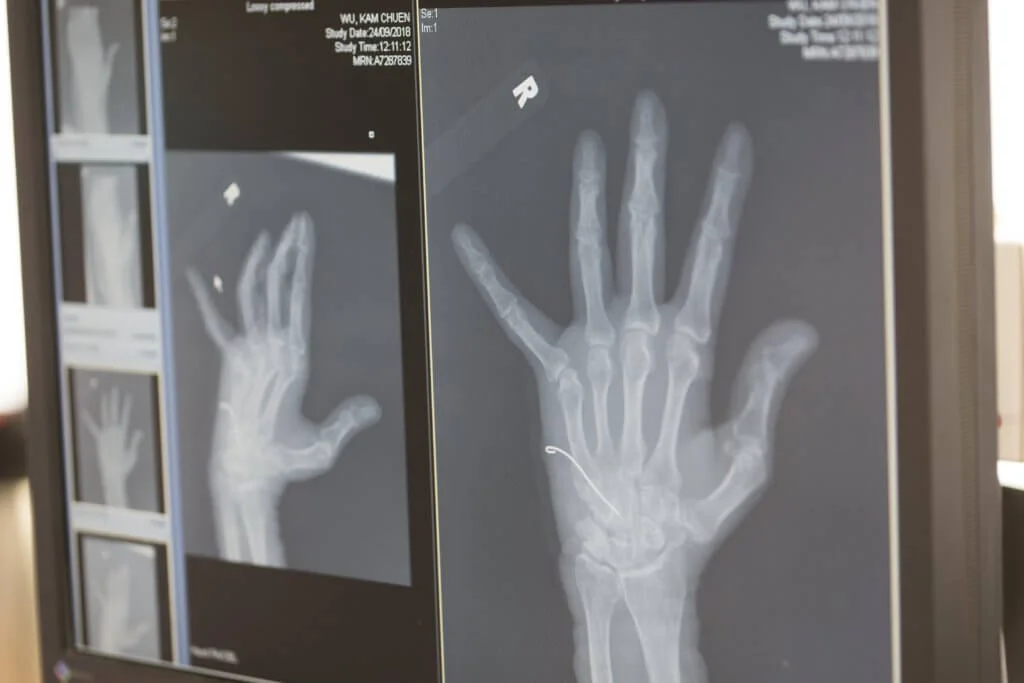

回首,何醫生不諱言,當年的探索過程備極艱辛,他把所有能找到的個案和資料都一一熟讀,而且決心把握每一個臨床機會,學習所有細節。每遇到一個手腕有疼痛問題的病人,何百昌都不厭其煩,仔細問診,每個部位逐點檢查,替病人照小型流動X光片,總要反反覆覆「左照右照」,目的是為了更好地了解病人的手部結構,做到「明察秋毫」,增加手術成功的把握。當經驗和理論不斷累積之後,終於給他碰上一個特殊的機會。何醫生為了減輕病人的痛苦,決定嘗試為那位病人進行一個手部的關節鏡手術──這在當年的手腕手術中可謂非常罕見。可惜,事與願違,他花了一個小時也找不到關節目標,結果那次手術尚未能以對病人更有利的微創形式完成。

話鋒一轉,原來作為外科名醫的父親,不僅在身心各方面幫助兒子,還親自幫過兒子做手術。那次,卓彥打球受傷,最初不以為意,後來發現手上的痛,歷久不癒,只好給父親看看。不料,父親一看,才知大事不妙。「一照X光,就發現卓彥的手指骨是粉碎型骨折,要動手術,偏偏他不想影響之後的音樂演出,只好先用石膏為他定型,待他表演後,再進行手術。」

何百昌說到這裏,不由得嘆道,兒子,就是醫生最怕也最難應付的病人,因為兒子不會聽話。「一般來說,醫生很少為最親近的人動手術,因為醫生面對自己熟悉的人,比較容易出現意外。」不過,原定手術因故推遲了,為免再生變數,也不想同事費心,何百昌幾經思量後,決定親自操刀。「幸好,這次手術過程算是相當順利。」何百昌說。